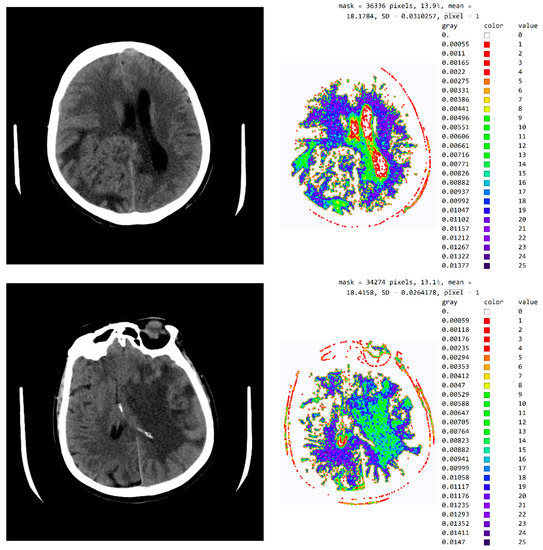

The evaluation of the developed model was conducted through an online questionnaire to determine whether smart visualization of medical images (SVMI) can contribute to the education of MDs in the radiology residency training program and undergraduate medical students. A total of twenty Physicians of the Department of Emergency Neuroradiology expressed their professional medical opinion when completing the questionnaire. Nine were neuroradiology/radiology specialists (45%) and eleven were MDs in the radiology residency training program (55%). All physicians agreed to participate in the research and did not have insight into the patient’s final diagnosis (Diagnosis of the disease after performing all the diagnostic methods provided by the protocol: Occipital right, in the region of PCA vascularization, observed zone of hypodensity, without differentiation of gray-white mass and flattened sulci diff.dg.acute ischemic stroke) after complete diagnostic methods, which included a post-contrast MDCT of endocranium, MDCT perfusion, and MDCT angiography. Therefore, a triple-blind review system was applied. No participants knew the physician’s opinion (before or after), or the patient’s official diagnosis, name, and surname, or the neuroradiologist who performed the examination. Additionally, all survey participants were asked questions according to the order of appearance of the images, starting with Figure 13a.

Figure 13.

(a) Non-contrast MDCT image of the endocranium; (b) SVMI of the non-contrast MDCT image of the endocranium; and (c) MDCT perfusion of the same cross-section.

Figure 13a shows a non-contrast MDCT image of the endocranium establishing a zone of hypodensity without clear differentiation of the gray–white mass on the occipital right, which corresponds to an acute ischemic lesion. Figure 13b presents our method of smart visualization of the medical images (SVMI) of the non-contrast MDCT image of the endocranium of the same cross-section. Figure 13c, after additional diagnostics of MDCT perfusion, shows a perfusion deficit that can be seen in the same region—occipital right—which confirms the diagnosis of an acute ischemic stroke.

On the presented non-contrast MDCT image of the patient’s endocranium (Figure 13a), 100% (nine) of radiology specialists noticed that changes in the brain had occurred based on their knowledge in the field of neuroradiology, which ranged from 3 to 15 years of experience for all radiologists who expressed their expert opinion. On the other hand, based on the non-contrast MDCT image of the endocranium (Figure 13a), 81.81% (nine) of the total number of MDs in the radiology residency training program who participated in the questionnaire did not notice the change, did not adequately characterize it, or did not give an adequate differential diagnosis. Table 1 shows the analysis of the physicians’ answers to the first question observing only Figure 13a.

Following smart visualization (SVMI) of the non-contrast MDCT image of the endocranium (Figure 13b), out of all physicians whose opinions were requested, 95% of respondents made an accurate diagnosis and confirmed the existence of pathological changes in density. However, one MD in a radiology residency training program answered incorrectly. Table 2 shows the analysis of the physicians’ answers to the second question observing only Figure 13b.